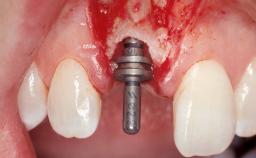

Immediate Flapless Placement of an Implant in a Maxillary Left Central Incisor Site

A 42-year-old female patient was referred to our clinic at the School of Dentistry of the University of São Paulo in November 2004, presenting a deficient restoration in the upper left central incisor. The clinical examination revealed no gingival retraction or any signs of gingival inflammation and, therefore, previous periodontal treatment was not considered. The patient presented a high lip line at full smile and a thin tissue biotype. This combination characterized a high-risk situation from an anatomic point of view, which required careful preoperative planning and cautious surgical execution.

| Placement Protocol | Immediate implant placement |